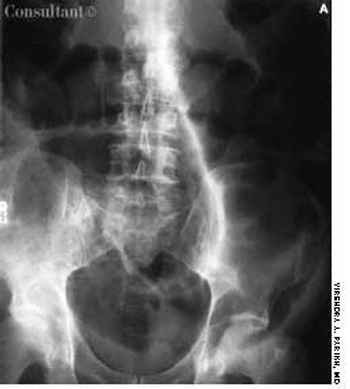

For 2 months, a 73-year-old man had experienced dysuria, pneumaturia, and foul-smelling urine. He had an attack of diverticulitis a year earlier. At that time, he underwent a barium enema study, which showed multiple sigmoid colonic diverticula with spasm.